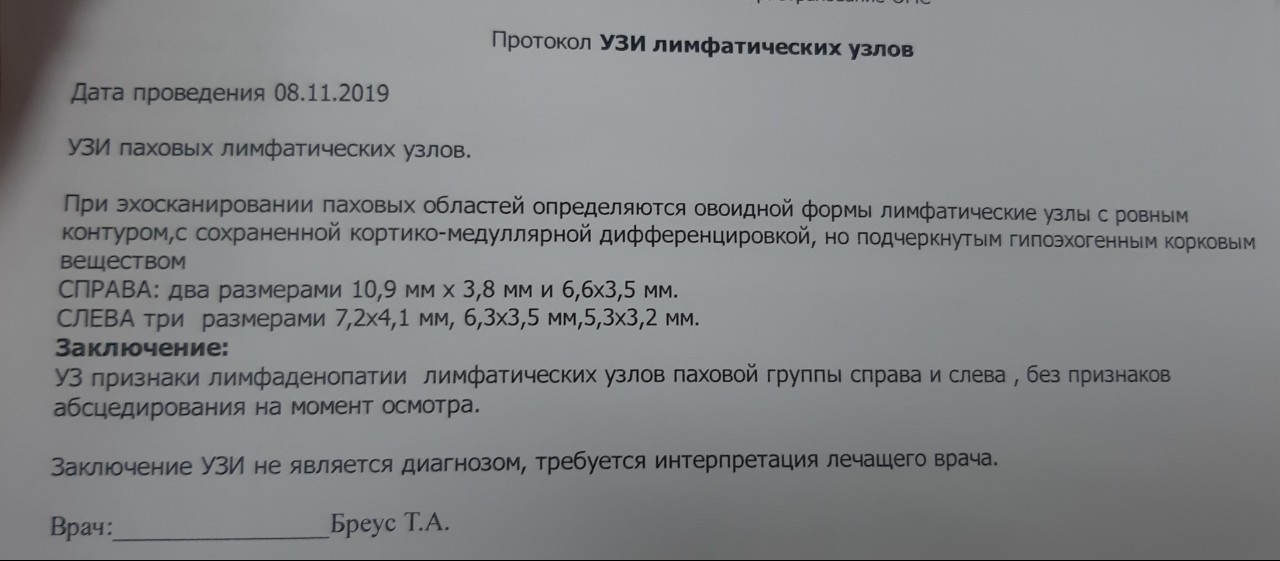

УЗИ лимфоузлов при лимфоме Ходжкина

Раздел: Образы вокруг